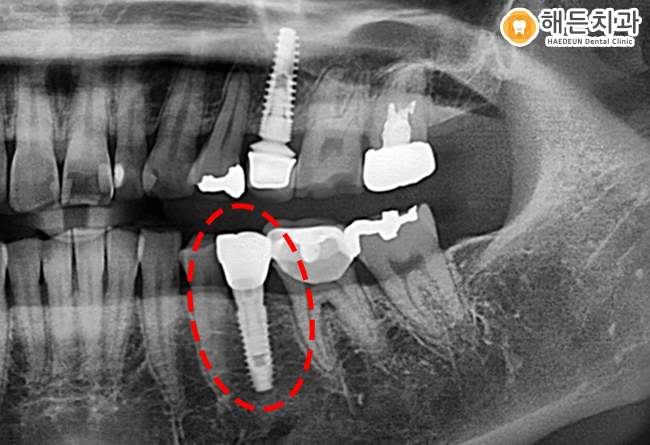

위의 환자분의 경우도 마찬가지인데요.

신경치료를 한 치아에 2차 충치가 발생했지만,

이에 대한 통증이나 불편함을 느끼지 못했습니다.

때문에 환자분께서는 방치하다가

치아가 부러져 아산임플란트치과에 내원해 주셨는데요.

먼저, 3D CT를 통해 환자분의 구강상태를 정밀하게 검사해 보았지만,

예상했던 것과 같이 2차 충치가 이미 심하게 진행되었고

치아 뿌리만 남아있는 상황이기 때문에

임플란트를 식립하기로 하였습니다.